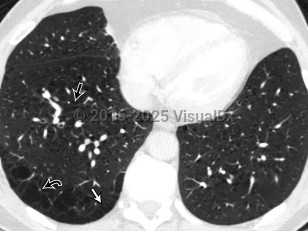

Chest pain, Dyspnea, 50-59 year old Female